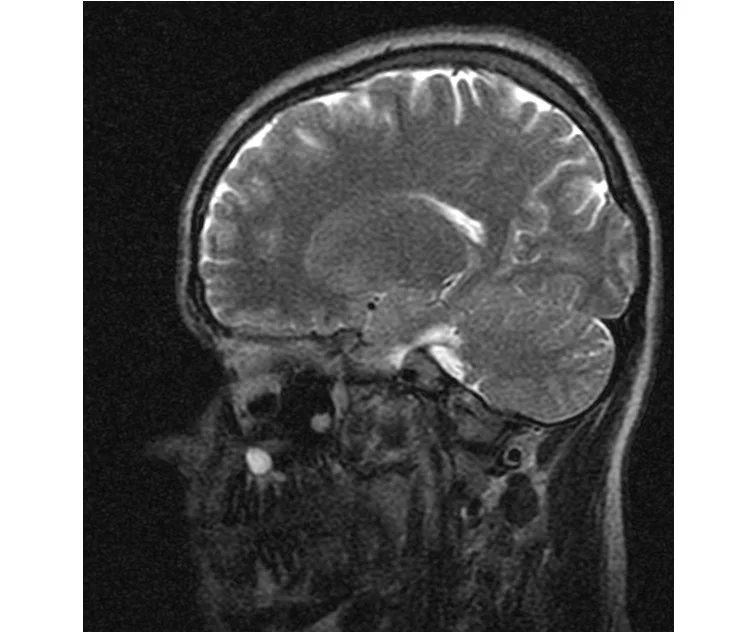

Меня смутил факт выдачи заключения через 10мин(наверно они у них зарание напечатаные)я не медик.достаточно мимолётного взгляда на снимки?А вы видете на них гидроцефалию? Я лиш спросил куда идти с результатами томографии?и не хотел никого роздражать.

Я попросил взглянуть на снимки и сказать видна.ли на них гидроцефалия?или куда обратится за консультацией по этому вопросу?В мрт снимках наверно розбирается любой нервопатолог(я так предположил)

Я уже говорил, что независимо от того, есть на МРТ гидроцефалия или нет, лечиться тебе нужно только в том случае, если есть какие-либо проявления болезни, иначе на все эти анализы можешь забить... Но давай все-таки разберемся с томограммой.

Итак, с самого начала томограмма обозначала срез какого-либо органа на определенной глубине, позволяла заглянуть вовнутрь. При компьютерной томографии аппарат делает десятки срезов головного мозга в разных направлениях и из этого множества срезов он моделирует полноценное объемное изображение мозга в натуральную величину. Обрати внимание, компьютер работает не с этими миниатюрными изображениями, а с трехмерной моделью в масштабе 1:1. Эту модель вдоль и поперек анализирует суперсовременный компьютер, выполняющий миллионы операций в секунду. Только ***** может пытаться перепроверить компьютер, ведь человеку не хватит всей жизни чтобы проанализировать то, что компьютер с тобой сделал за 10 минут. Я хочу, чтобы ты это понял!

Ты разместл здесь несколько миниатюр и хочешь, чтобы врач по ним создал полноценное объемное изображение в натуральную величину, а потом осмотрел его со всех сторон и дал заключение? Но ведь это невозможно. Это просто насмешка над врачом, это издевательство над здравым смыслом. Принеси Букеру уменьшенный в 50 раз снимок зуба и спроси у него, в каком состоянии там корневые каналы. Или давай я дам тебе скрин со спутниковой карты города и попрошу тебя описать, какого цвета и какой модели запечатленная со спутника машина, какой у нее гос.номер, сколько в ней пассажиров, сколько из них мужчин и сколько женщин...

Надеюсь, ты понимаешь, что это невозможно. И воссоздать по приведенным тобой аватарам полную картину мозга тоже невозможно. Пойми, если уж называть вещи своими именами, то ты запостил полнейшую ***ню! Ты не хотел никого обидеть, ты ведь сам не ведал, что творил. Ты продемонстрировал полнейшую медицинскую безграмотность и полное невежество, но претензий к тебе нет. Ты ведь не один такой. Ты пожелал того, что сделать невозможно, и тут же у тебя нашлась сочувствующая, некая П., которую, по большому счету, надо бы послать в П., коль уж она считает, что врач должен тут сделать немедленно и бесплатно то, что делает немецкий компьютерный томограф ценой в миллионы долларов.